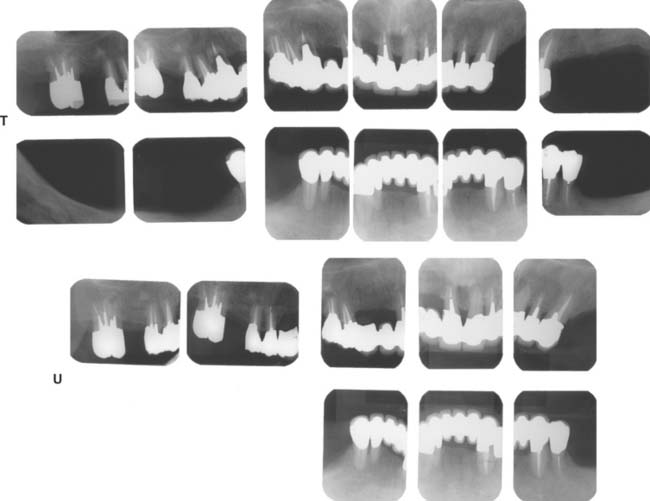

Fig. 32-42 This patient presented with multiple failing restorations and severely compromised function (Treatment X). A to E, Preoperative photographs. F to J, Posttreatment photographs. Where possible, I-bars were used to minimize clasp visibility. Also note the extensive use of metal occlusal surfaces. When prostheses are designed for dentitions with compromised crown/root ratios, precise adjustment of the occlusion and anterior guidance components is critical. K to Q, Seventeen-year follow-up photographs. Note that the maxillary canine was lost and the existing retainer was modified into a pontic through the addition of composite resin. Additional endodontic treatment was needed as time passed. R, Preoperative radiographs. S, Postoperative radiographs. T, Eight-year postoperative radiographs. U, Seventeen-year postoperative radiographs. A fixed dental prosthesis (FDP) was fabricated, replacing the missing tooth #3 with teeth #5, #4, and #2 as abutments. The teeth were prepared with minimal taper, and the castings exhibited good retention. After 10 years, the FDP failed when tooth #2 became dislodged, possibly as a result of the additional loading by the removable dental prosthesis (RDP). Tooth #2 and the pontic were removed, endodontic treatment was performed, a new crown was fabricated, and the #3 pontic was incorporated in a new RDP. Tooth #6 was lost as a result of internal resorption and caries. Initially, the tooth was discolored, but the lesion was inactive, and the attempt to save it failed after 8 years. Its guarded prognosis was discussed as a significant risk factor before treatment initiation. This suggests that teeth with a guarded prognosis can be maintained if attention is paid to the principles of casting adaptation and occlusion.